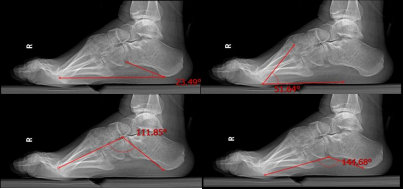

腓骨肌萎缩症是一种罕见病,2018年5月国家卫生健康委员会等五部门联合制定《第一批罕见病目录》中使用该名称。腓骨肌萎缩症主要是由于遗传因素出现下肢的渐进性活动性障碍,由于肌肉肌力的变化,导致足部及踝关节活动出现异常,手术治疗的原则是纠正足部畸形,重建和平衡足踝肌力。手术方案包括肌力平衡手术(各种类型的肌腱转移术)、软组织松解与矫形(足底筋膜切开术)、跟骨截骨矫形、腓肠肌复合体处理、踇趾矫形或其他足趾矫形手术。手术治疗有利于恢复患者的生活质量。